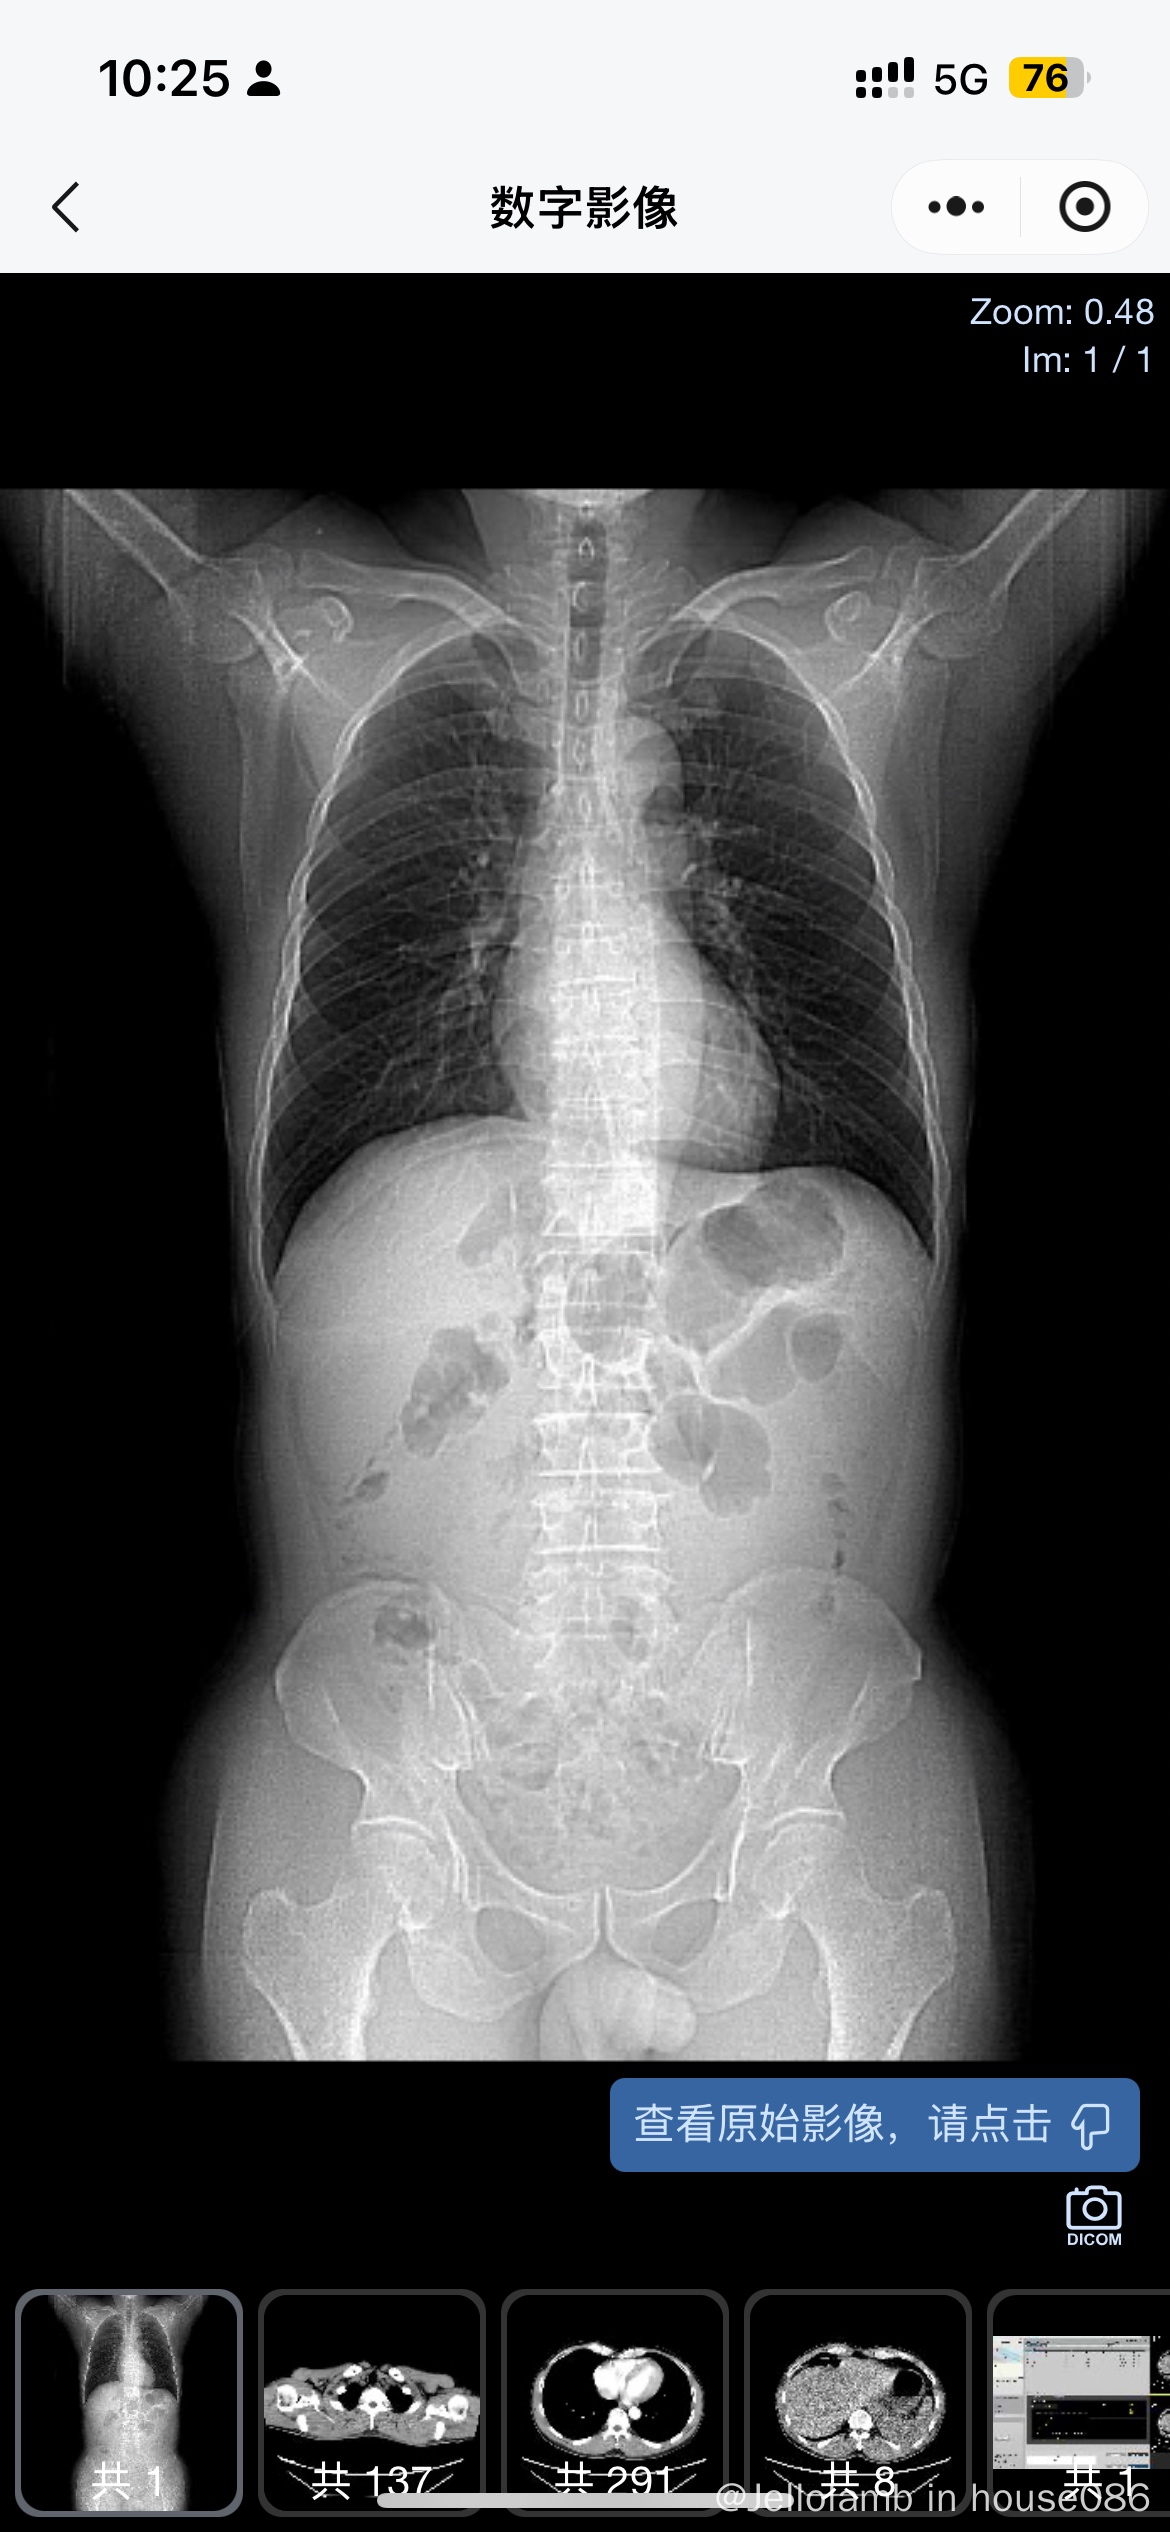

淋巴瘤可能

我爸爸做完加强ct后的结果,疑似淋巴瘤,想问一下有没有同样的情况呀这是在腹部长了东西且挺大的,同样情况的是怎么样治疗的呀?活检还没做,正在预约。